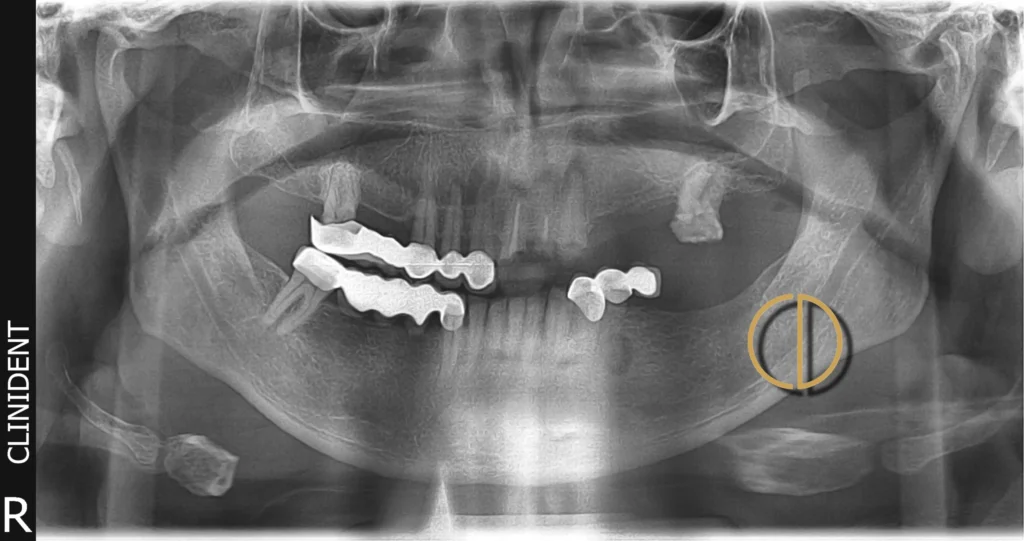

Páciensem azzal a problémával érkezett, hogy a meglévő felső híd és több fog rendkívül rossz állapotban volt, a jobb felső híd a fogakkal együtt kitört, és csak a menthetetlen, letört fogak gyökerei maradtak. A teljes száj állapotát figyelembe véve a kezelés komplex rehabilitációt igényelt a felső és az alsó fogsorban egyaránt.

A teljes állapotfelmérés után megállapítottuk, hogy a felső híd tartó fogai nem menthetők, ezért mindet el kellett távolítani. Az alsó fogsor több foga is rendkívül rossz állapotban volt, így itt is több foghúzás vált szükségessé.

- Fog implantátumok beültetése: 6 db a felső, 4 db az alsó állcsontba.